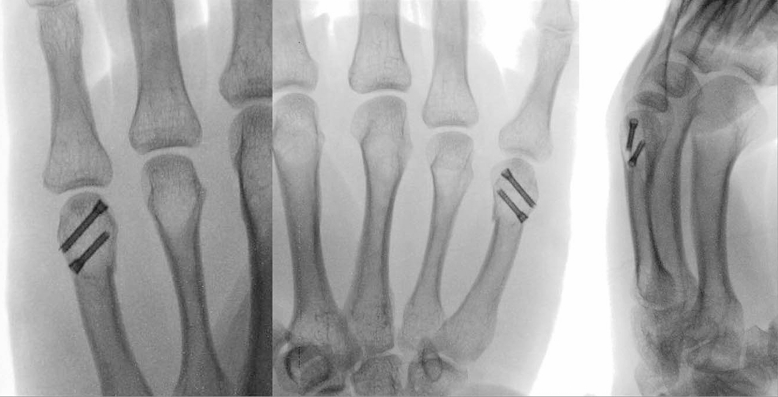

7. Percutaneous Intramedullary Fixation for First Metacarpal Base Fractures